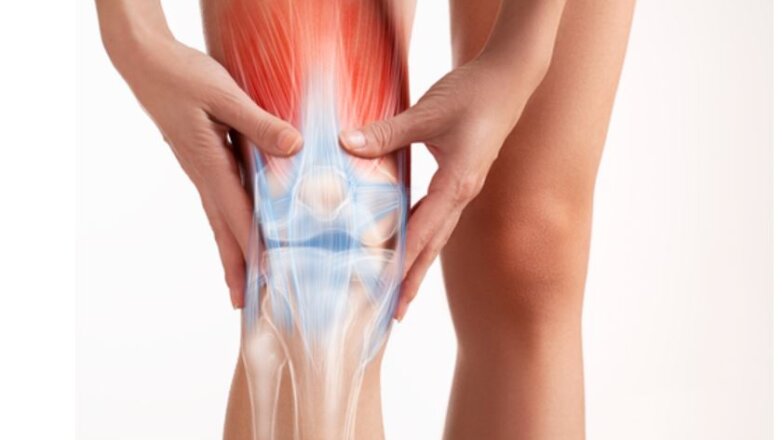

Η ολική αρθροπλαστική γόνατος αποτελεί τη μοναδική οριστική θεραπεία της οστεοαρθρίτιδας τελικού σταδίου.